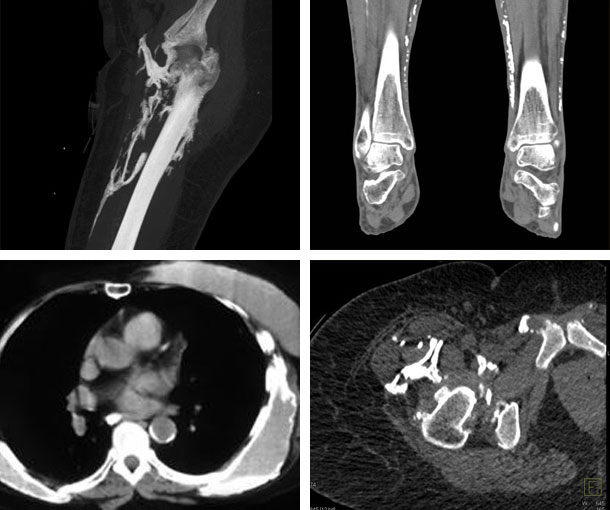

Dermatomyositis CT Findings

- Soft tissue thickening

- Soft tissue calcification

- Enlargement of the pectoralis major muscle

- Enlargement of the muscles along the abdominal wall